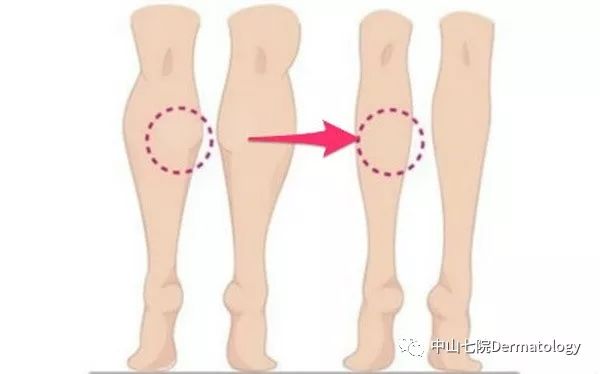

另外,肌肉长期得不到神经的信号就会萎缩变小,那些通过减少肌肉体积实现的轮廓塑性(瘦脸,瘦腿,瘦肩)就分分钟被get啦

(2)轮廓塑性:以瘦脸为例,一部分人群脸大主要是因为咬肌肥大,肉毒素通过选择性萎缩部分肌肉从而让你瘦脸不是梦!!瘦腿瘦肩是一个道理,只是作用于不同的肌肉。